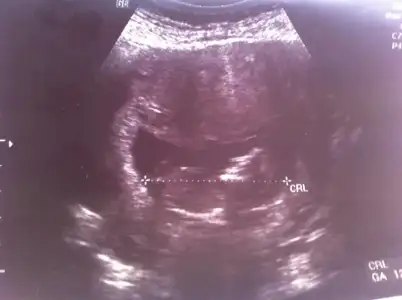

cnm burda kac haftalik sayet 12 ve uzeri ise ctrl cizgisinin altinda bir cikinti goruyorum

paralel gibi ama eminde degilim cunki hemen ustunde bi cikinti daha var net degil yani

Orkdm canım resim kağıdını elime aldım baktım ctrl çizgisinin altındaki sırta çok yakın gibi geldi o nub olabilir miki acaba,neyse artık bi sonraki kontrolde öğreniriz inşaallah,Saol ilgilendiğin için:)

evet bende oyle gordum ki oysa kesin kiz